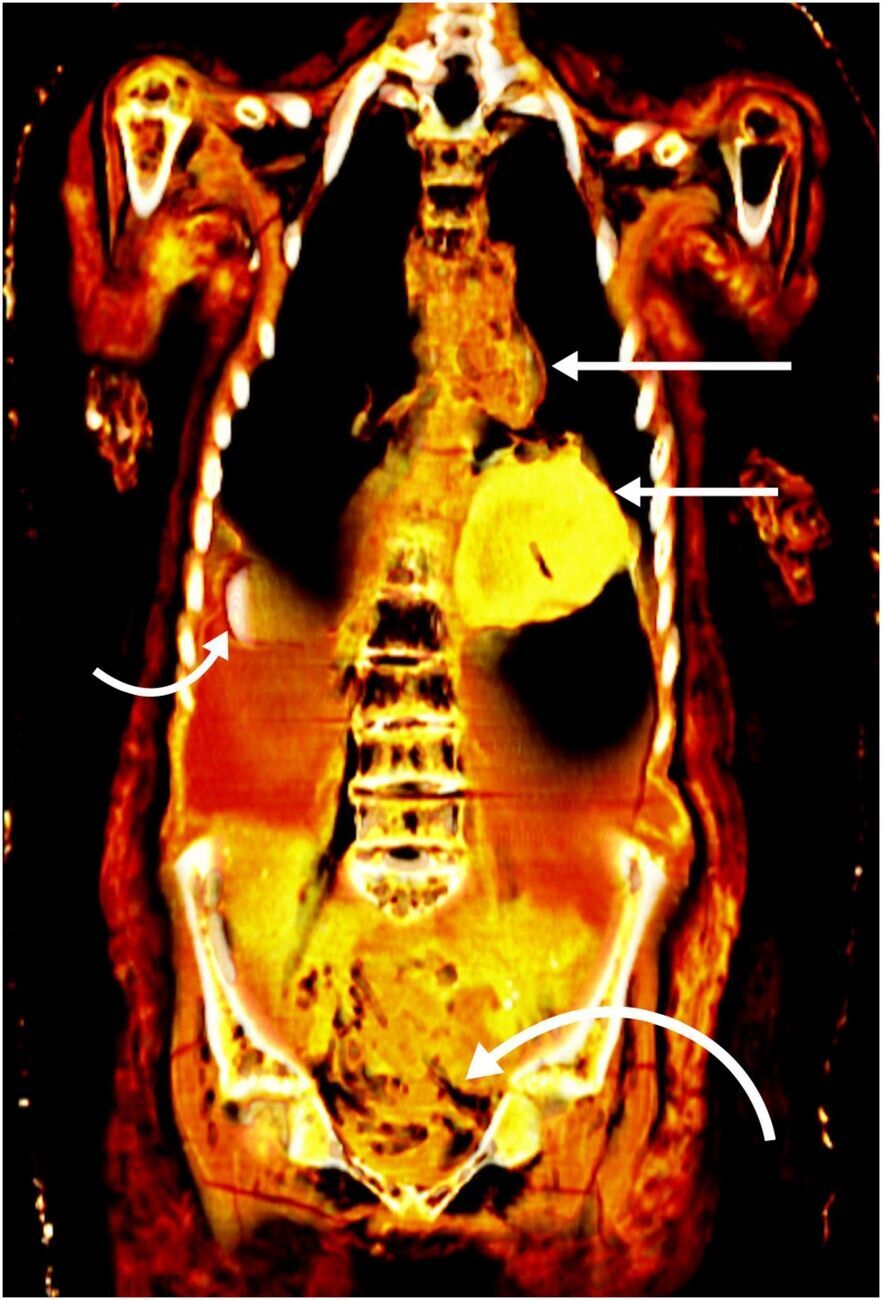

На знімках, які одержали завдяки томографії, науковці побачили у грудній клітці мумії золотого жука-скарабея у формі серця, а у черепі – золотий язик. Окрім того, виявили, що в саван було загорнуто 49 амулетів, більшість із яких теж були золотими.

Науковці встановили, що тіло досліджуваної ними мумії належало підлітку, який помер у віці 14 або 15 років. Команда дослідників, вивчивши стан зубів і кісток, припускає, що він був представником так званої золотої молоді. Про це також свідчить удосконалений процес муміфікації, під час якого було видалено мозок і внутрішні органи.